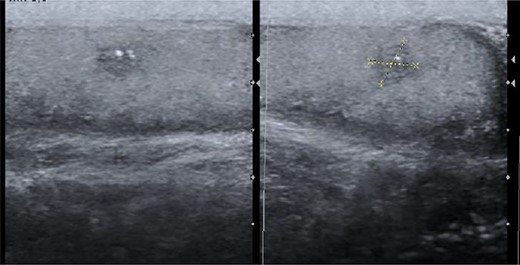

After this diagnosis, the patient was re-evaluated, maintaining a normal testicular examination; tumour markers where rechecked: β-hCG 243 U/L, α-fetoprotein (AFP) 2.06 ng/mL and lactate dehydrogenase (LDH) was normal; sonography identified right testicle heterogeneity with a nodular hypoechoic area with internal calcifications (Fig. 3) and thoracic CT showed no relevant abnormality.

Scrotal ultrasound with a heterogeneous nodule with microcalcifications.